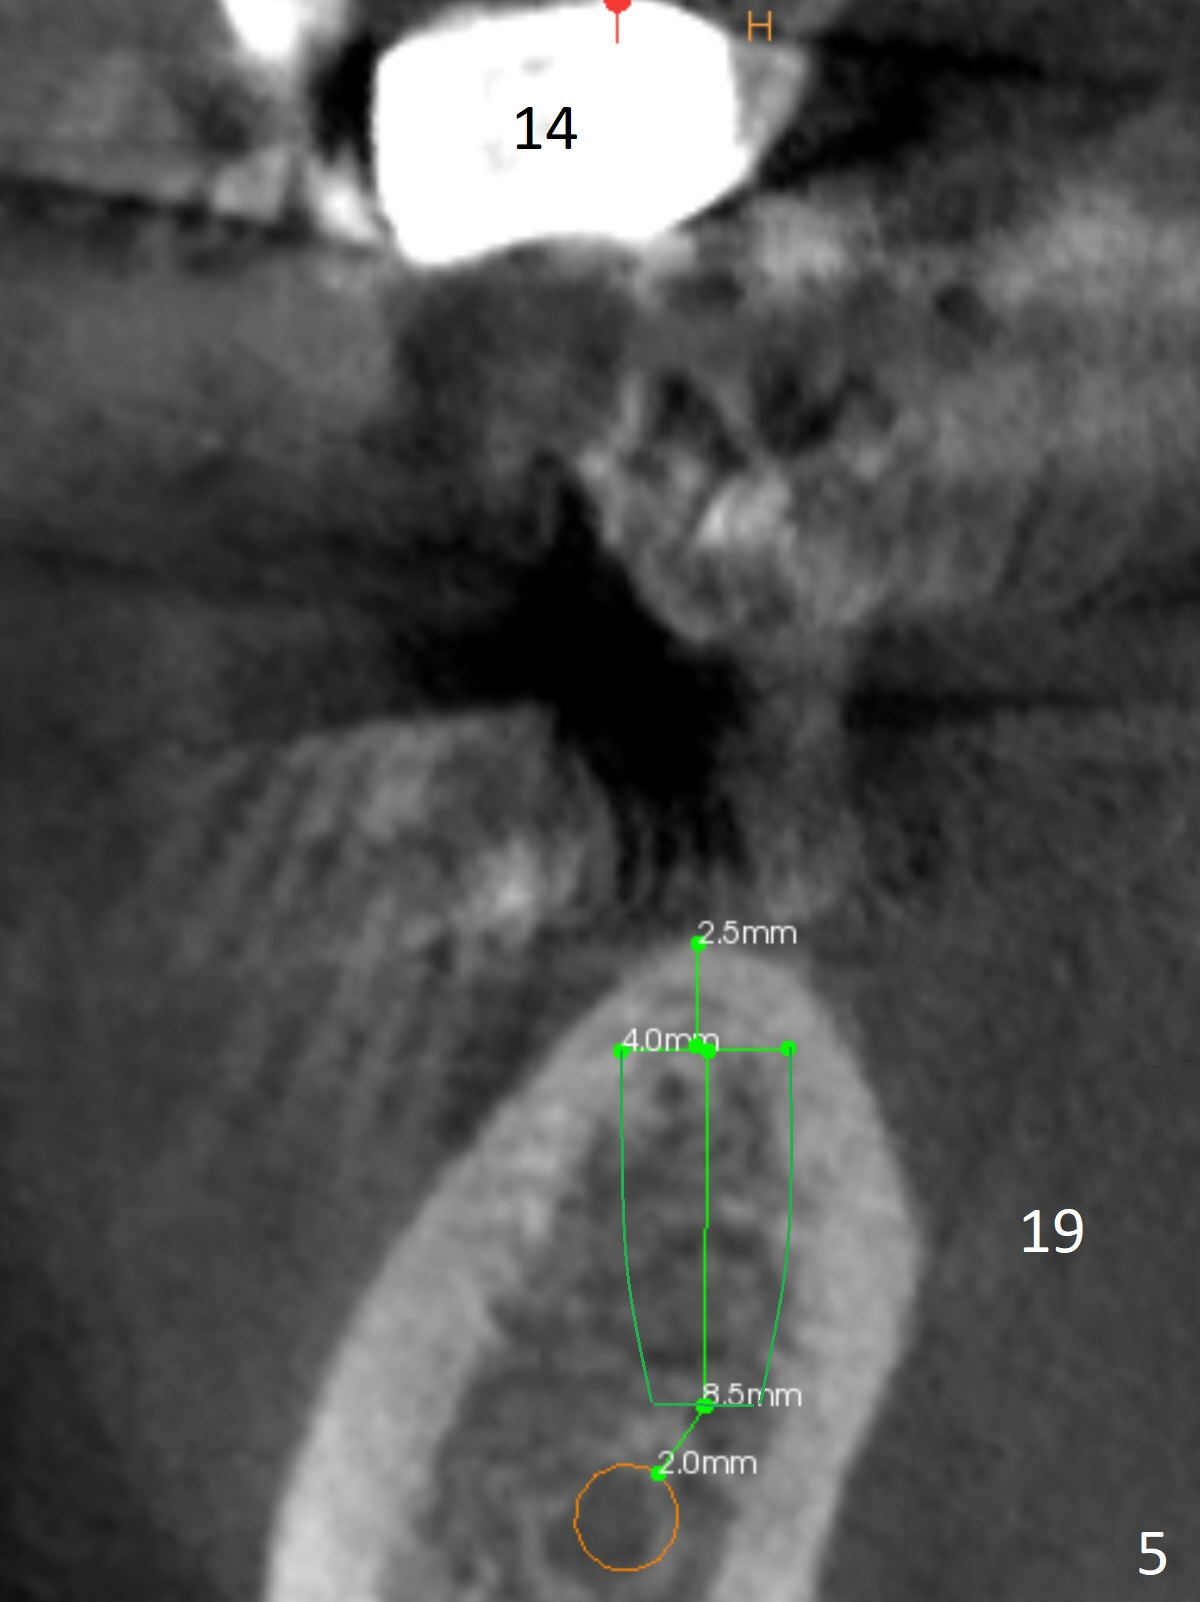

A healthy 37-year-old woman has 3 missing lower molars (Fig.1 panoramic view from CBCT). She has had implants at #8 and 10. The bone height for these molars is shown in Fig.2. The 1st molar ridges appear to be narrow (Fig.4,5,6), as compared to that of the 2nd molar (Fig.3 (B: buccal)). Ridge reduction seems to be necessary for the 1st molar sites prior to implant (green area) placement or deeper osteotomy.